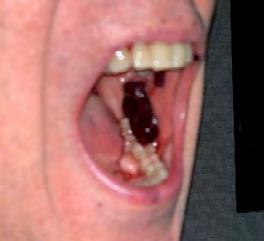

Case 1 occurred in a 69-year-old male who presented to his oral surgeon with the chief complaint of “blisters” in his mouth after being seen by his dentist. His medical history was significant for Graves disease, hypertension, prostate cancer and the corresponding treatment (radiation therapy, hormone therapy and gynecomastia surgery). Ten days post-gynecomastia surgery, he had a fever and was given sulfamethoxazole-trimethoprim by his surgeon. Clinically, the oral surgeon visualized a large purpura of the left buccal mucosa (Figure 1). The patient was on Bactrim for eight days before developing oral lesions.

Case 2 occurred in a 75-year-old female who presented to her dentist with the chief complaint of developing “blood blisters” in her mouth after having difficulty swallowing her sulfamethoxazole-trimethoprim pill the night before. At the visit with her dentist, she reported that her blisters were “improved” that morning, but that she also had “mosquito bites” on her arms. Clinically, the patient presented with purpura and petechiae of her right buccal mucosa and labial mucosa and petechiae of the dorsal tongue and forearms (Figures 2-6). The patient was on Bactrim for 10 days before developing oral lesions.

Figure 1. Case 1: Purpura of buccal mucosa. Figure 4. Case 2: Petechiae involving tongue. Figure 2. Case 2: Purpura and petechiae of right buccal mucosa and dorsal tongue. Figure 5. Case 2: Petechiae of upper labial mucosa. Figure 3. Case 2: Purpura and petechiae involving labial mucosa.

Figure 6. Case 2: Widespread petechiae of arms of patient.